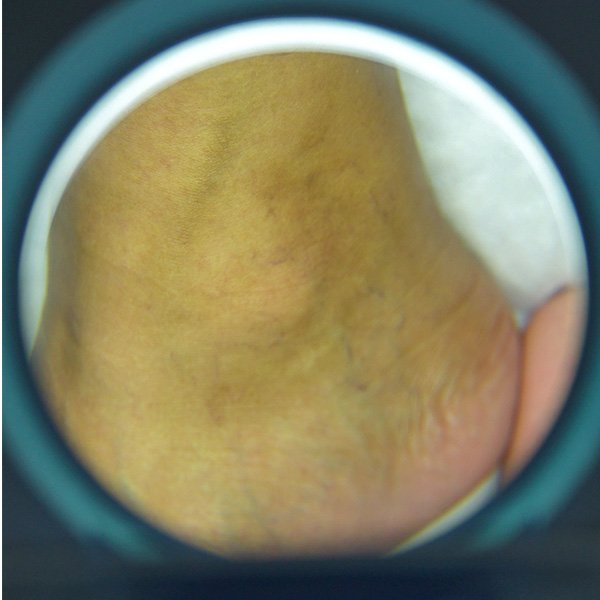

Melia’s Sclerotherapy treatment helps women fade varicose veins, relieve discomfort, and feel confident in their legs again.

• Visible veins that make you avoid wearing shorts, skirts, or dresses

Smooths and fades visible veins for more confident skin